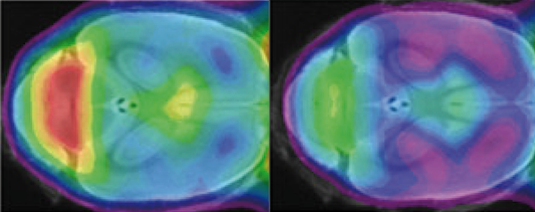

Una modifica minima nella TREM2 genera una riduzione marcata dell'attività fagocitica delle cellule microgliali nel cervello dei topi mutanti (verde, a destra) rispetto al controllo (giallo e rosso a sinistra). Fonte: Haass Lab.L'impatto preciso delle microglia nelle malattie neurodegenerative come l'Alzheimer e il Parkinson è ancora poco chiaro.

Inoltre, la mutazione ha conseguenze catastrofiche per il metabolismo energetico. Il cervello normale è totalmente dipendente dal glucosio come fonte di energia, ma la perdita della funzione della TREM2 porta ad una diminuzione significativa del consumo di glucosio nel cervello mutante. Inoltre il flusso di sangue al cervello nell'insieme è notevolmente ridotto.